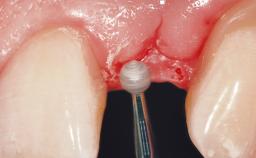

A 36-year-old female patient was referred for the replacement of the upper left central incisor (tooth 21), which had fractured. Although the tooth had been asymptomatic for many years, the crown began to loosen, at which time she presented to her dentist for an assessment. Teeth 21 and 22 had both been endodontically treated many years previously. She was a healthy individual and a non-smoker.

The crown of tooth 21 was splinted to the adjacent teeth with composite resin, and the gingiva was inflamed.